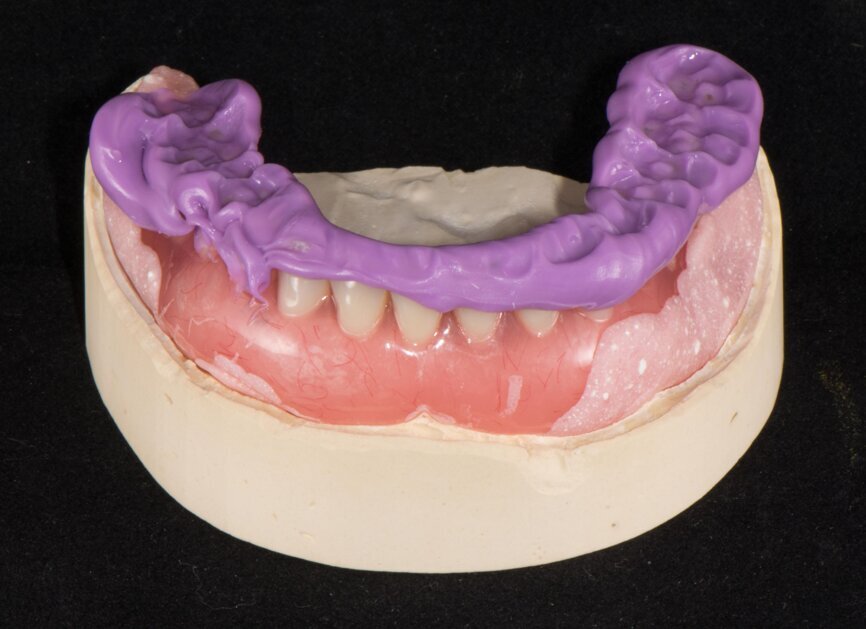

The planning included several steps. First, the hopeless teeth in the mandible were to be extracted, followed by delivery of a complete immediate denture, as they did not offer any stable support for a surgical guide. Six weeks later, owing to the lack of keratinised tissue in the premolar regions, apical repositioning and a free gingival graft were performed (Fig. 2). After 1.5 months, the denture was relined with a mixture of barium sulphate and resin, transforming the denture into a radiographic stent (Fig. 3). Another CT scan was recorded with the stent in the mouth (Fig. 4). The stone cast of the stent was poured (Fig. 5), giving us the actual clinical picture of the mucosa, and both cast and stent were scanned to obtain their STL files. Using the coDiagnostiX planning software, the radiopaque saddle of the stent and the STL scan were matched, which also allowed the stent to be matched with the cast as positive and negative, thus, giving us the soft-tissue volume. Implants were planned in a prosthetically driven manner at sites #34, 32, 42 and 44, with corresponding screw-retained abutments (Fig. 6).

Because of an open-flap procedure owing to the lack of keratinised tissue and the placement of long implants (all Straumann BLT Roxolid, SLA implants; 4.1 × 12.0 mm), it was decided to make two surgical guides: first, a mucosa-supported guide only for drilling the template fixation pins (Straumann; Fig. 7); and second, a pin-supported guide for fully guided implant placement (Fig. 8).